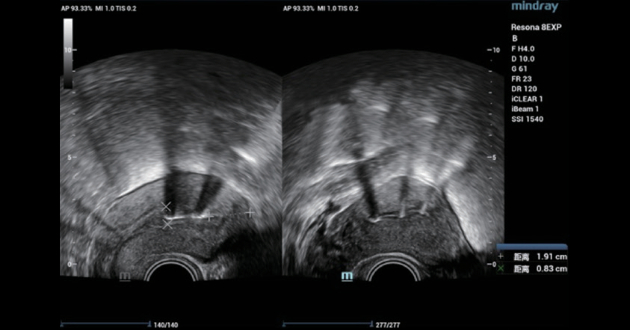

Case 3 - IUD rotation

A 30-year-old female, IUD insertion three months ago, with intermittent abdominal pain and abdominal distention for one month. The 2D ultrasound showed no obvious abnormality, but the 3D ultrasound suggested a rotation of the IUD (Figure 5 and Figure 6). The patient's symptoms were relieved after replacing the IUD.

intrauterine-device-fig6-pc

Figure 6. 3D ultrasound showed IUD rotated